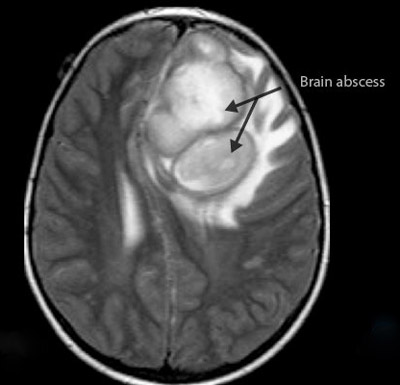

Диагностика абсцесса мозга включает в себя нейровизуализацию, чаще всего с помощью МРТ или КТ, что позволяет точно определить локализацию и размеры образования. Лечение, как правило, комбинированное: оно включает антибиотикотерапию и, в некоторых случаях, хирургическое вмешательство для дренирования гноя. Врачи подчеркивают важность ранней диагностики и своевременного лечения, так как запущенные случаи могут привести к серьезным осложнениям и угрожать жизни пациента.

Диагностика включает нейровизуализацию, чаще всего с помощью МРТ или КТ, что позволяет точно определить размер и расположение абсцесса. Лечение обычно требует комбинированного подхода: антибиотикотерапии и, в некоторых случаях, хирургического вмешательства для дренирования гноя. Ранняя диагностика и адекватное лечение играют ключевую роль в предотвращении серьезных осложнений и улучшении прогноза для пациента.

- Компьютерная томография (КТ) головного мозга — доступный и высокочувствительный метод. Без контрастного вещества он выявляет лишь области с пониженной плотностью. Четкость структуры патологического очага достигается при введении рентгеноконтрастного вещества.

- Магнитно-резонансная томография (МРТ) головного мозга — более точный метод, который может обнаружить абсцесс на ранних стадиях, точно определить локализацию гнойного очага и распространение инфекции в подпаутинное пространство и желудочки. МРТ достаточно для правильной постановки диагноза и дифференциации абсцесса от других патологий.